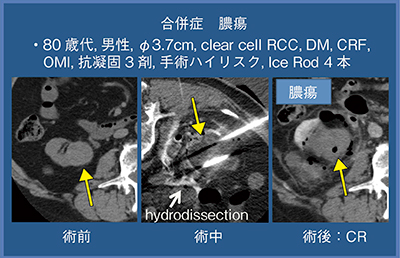

症例3(80歳代,男性)は,腫瘍径3.8cmのclear cell RCCで,糖尿病,慢性腎不全,陳旧性心筋梗塞があり,抗凝固薬3剤服用の手術ハイリスク症例のため凍結療法を施行した。ニードル4本にて治療を行ったが,傷の治りが悪く膿瘍が生じたため,ドレナージと抗菌薬で治療を行っている(図6)。

図6 症例3:合併症 膿瘍(80歳代,男性)